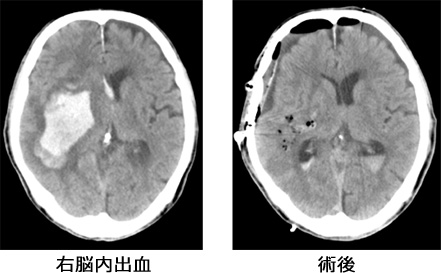

①開頭血腫除去術

開頭術を行い、脳の中の血腫を除去し、活動的な出血が認められれば止血を行います。状況によって頭の骨を外した状態で集中治療室に戻ることもあります。